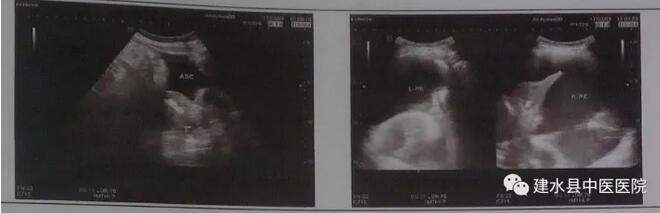

患者女,46岁,因“尿频、尿急、下腹部胀痛、胸闷”就诊,2017年2月22日行CT检查显示:右侧胸腔中等积液,左侧胸腔大量积液,邻近右肺下叶部分不张,左肺下叶完全性不张。腹腔大量积液。给患者行胸腔及腹腔穿刺术,术后病理示:肿瘤细胞来源于卵巢的可能性大,多考虑来源卵巢的浆液性乳头状癌,于3月6日、3月10日、3月20日、3月23日、4月1日行5次胸腔内“顺铂灌注热化疗”,并行TC方案全身化疗,化疗后未见明显副反应,2017年4月26日到院复查腹水消失,左侧有少量胸水,2017年5月24日到院复查,胸腹水消失,患者生存质量得到良好改善。影像结果展示如下:

2017年3月3日入院检查,检查部位:胸腹水,超声提示:腹腔内少量积液,右侧胸腔大量积液,左侧胸腔中等量积液。

2017年4月26日,到院复查,检查部位:胸水,超声提示:左侧胸腔少量积液。

2017年5月24日到院复查,检查部位:胸腹水,超声提示:双侧胸腔及腹腔未见明显积液声像。(肿瘤科 建水县中医医院)